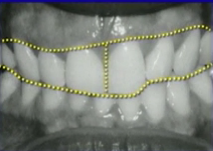

Restoring patients with pathway wear requires aligning the “dental” and “neuromuscular” envelopes of function. Harmony between the two is the key to predictable, long-term success.